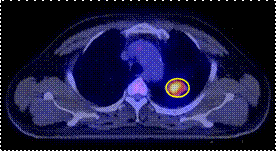

Hình 1: Phim X-quang tim phổi: có đám mờ phổi trái

(trong vòng tròn màu vàng)